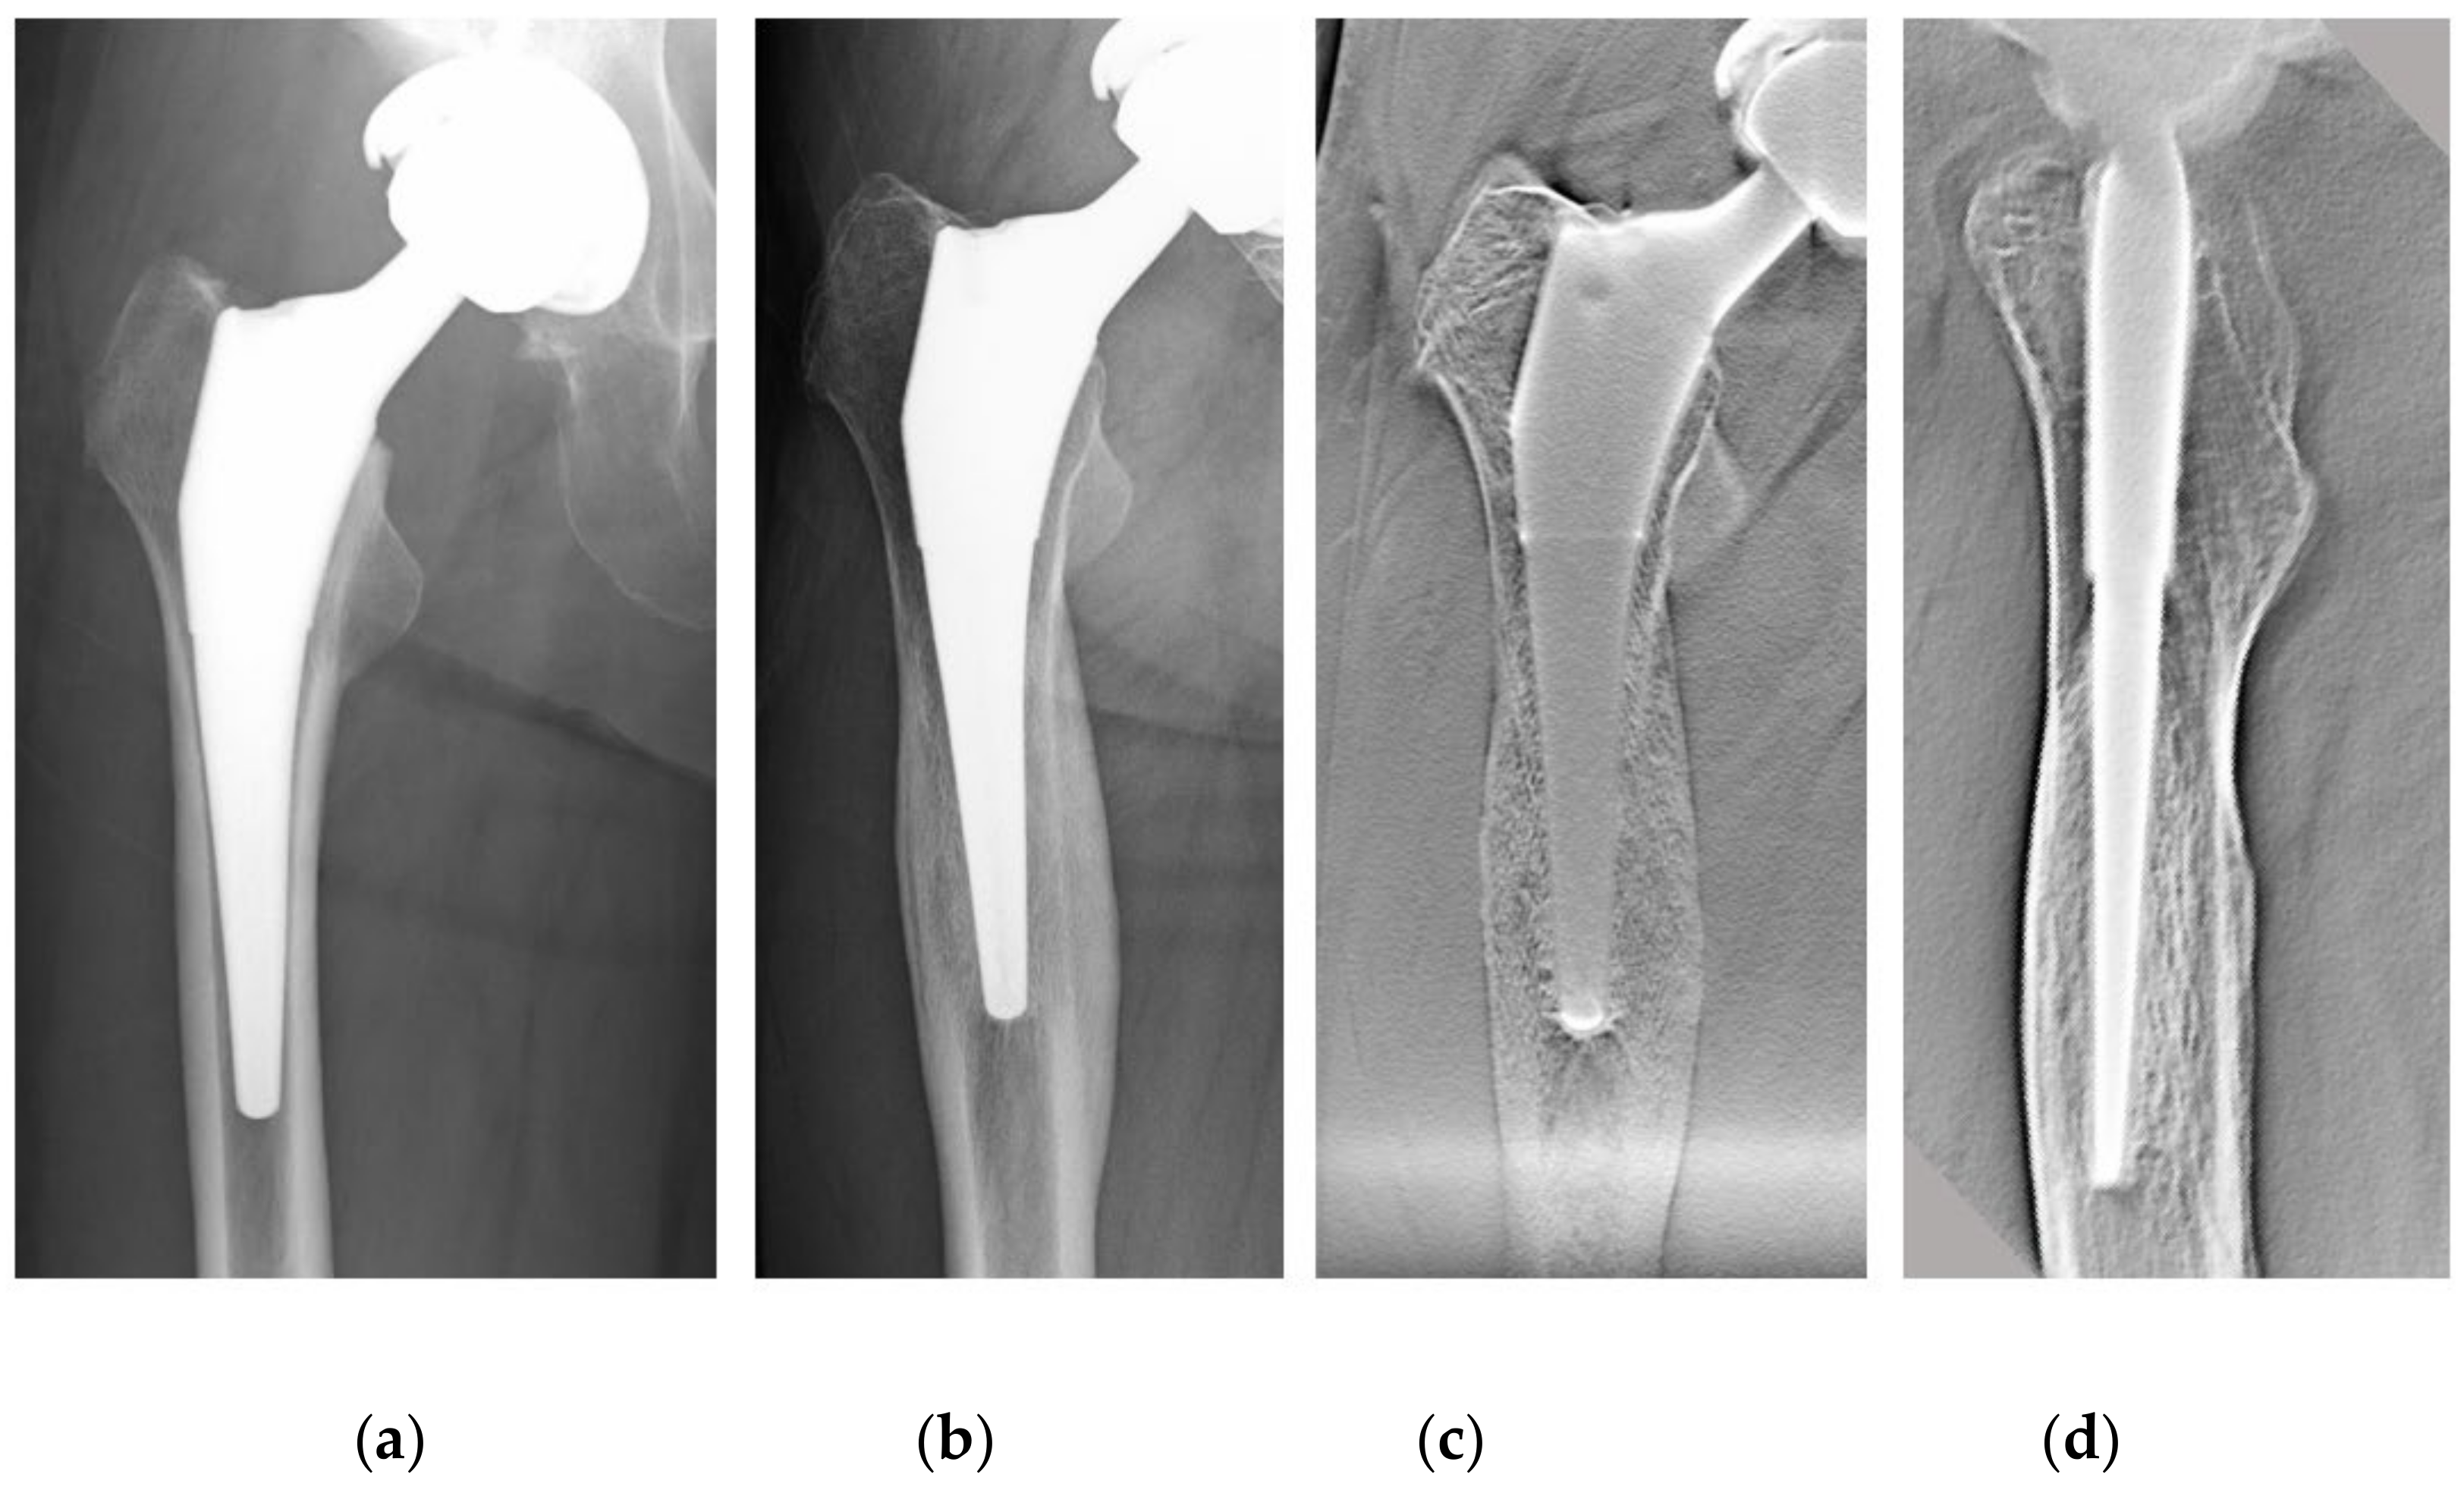

The loosening of the prosthesis may not be visible either clinically or by imaging, and reliable imaging methods are needed for early diagnosis [8,9]. Plain radiography and computed tomography (CT) are the most widely used methods for evaluating bone reactions around cementless stems [10,11]. However, plain radiography is difficult to reproduce owing to the inconsistent body position and the lack of spatial resolution in the depth direction, making detailed image evaluation difficult [12,13]. CT also distorts the bone–implant interface due to metal artifacts, and the radiolucent line (RLL) may be underestimated or not identified [14]. Therefore, we focused on DTS to evaluate the stem in detail. We used DTS to diagnose hip loosening and evaluate cortical hypertrophy and biological fixation and applied it to preoperative planning for THA revision (Figure 1).

Figure 1.

A 61-year-old female patient after THA using a tapered wedge stem. (a) Plain radiographs one month after THA. (b) The same patient 6 y later. There was cortical hypertrophy at Gruen Zones 3 and 5. (c) DTS (AP view) at the same time as (b). Cortical hypertrophy was observed more clearly. (d) DTS (lateral view) at the same time as (b). Heterogeneous loss of permeability is seen in the cancellous bone distal to the porous coating. THA, total hip arthroplasty; DTS, digital tomosynthesis; AP, anterior–posterior.